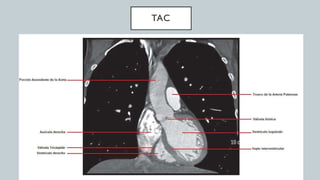

El documento detalla la anatomía del corazón y su ubicación en la caja torácica, incluyendo estructuras como las aurículas, ventrículos y arterias. También se abordan técnicas de diagnóstico por imagen, como radiografías y TAC, para visualizar la morfología cardíaca. La información está dirigida a estudiantes de medicina y profesionales interesados en la anatomía cardíaca.